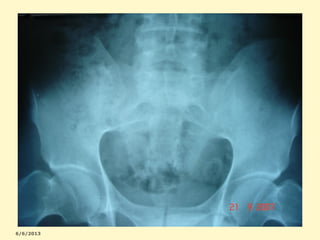

Sacroieíte bilateral + sínfise púbica

ESCLEROSE + ALARGAMENTO +IRREGULARIDADE

Sacroileíte+sínfise+coxo-femurais

Sacroileíte bilateral com esclerose e

estreitamento das articulações sacro-ilíacas